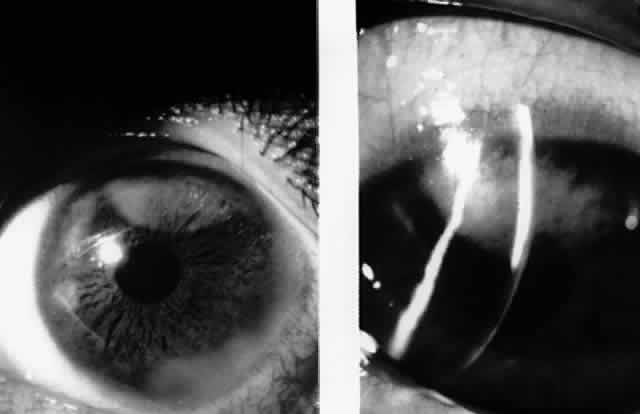

In 1990, Pflugfelder and associates reported a 66-year-old woman with bilateral, pleomorphic, ring-shaped, anterior stromal opacities which developed 3 months after initial onset of concurrent bilateral, dendritic epithelial keratitis (Fig. 5).74 Dendritic epithelium removed by impression cytology at the second recurrence of epithelial disease bound monoclonal antibody to EBV early antigen-diffuse and contained EBV genomic sequences as shown by PCR. Corneal epithelial cultures for HSV were negative on two occasions. EBV serology test did not indicate acute infection, and thus confirmed the earlier impression of Matoba and associates, that EBV keratitis may follow viral reactivation from the chronic carrier state.

Fig. 5. Peripheral corneal dendrite (arrows) in a 66-year-old woman who later developed ring opacities of the anterior corneal stroma.